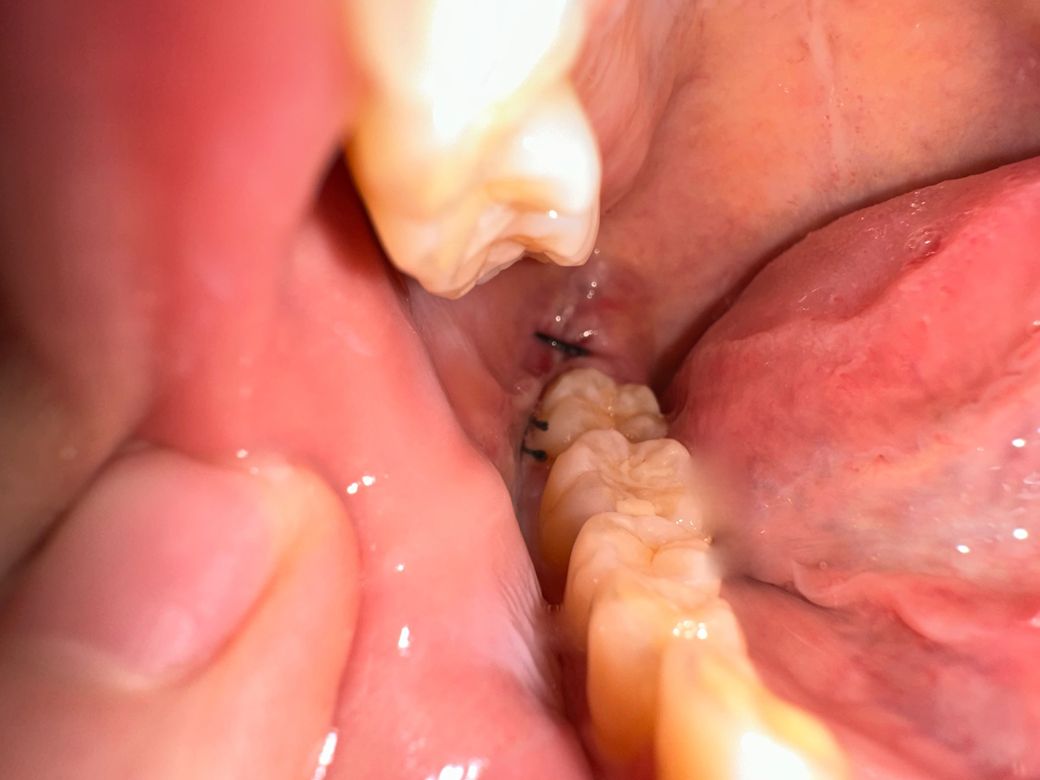

매복사랑니 잘 아물고 있는지 봐주실 수 있을까요

지금 뽑은지는 4일차입니다 이런 상태인데 잘 아물고 있는지 모르겠고 사람들마다 원래 실밥은 좀 다르나요 ?̊̈ 제 실밥만 이런가 싶어서요 잘 아물고 있는지 드라이소켓은 없는지 궁금합니더 지금 현재 좀 염증이 차있어거 턱이랑 볼쪽이 멍울처럼 딱딱하고 많이 부어있어요 ㅠㅠㅠ 괜찮은거겠죠? 치과에 가서 염증이 차있다고 하면 뭐 치료법이 따로 있나요? 입이 잘 안벌려지는건 염증때문일까요

• 2번 째 사진

봉합상태도 굉장히 좋고 염증소견도 없어보입니다.

발치후에 많이 붓고 아플 수 있는데요 때에따라 환자분처럼 입이 안벌어지기도 하지만 대부분 실밥을 풀 때 쯤에는 많이 호전이 됩니다.

그리고 발치후에 볼쪽을 눌러봤을때 덩어리처럼 단단한게 만져지는 경우도 있는데 상처가 나면 흉터가 생기는 것 처럼 안쪽에도 흉터가 생겨서 그렇다고 생각하시면 되는데요. 보통 시간이 지나면 점차 옅어집니다.